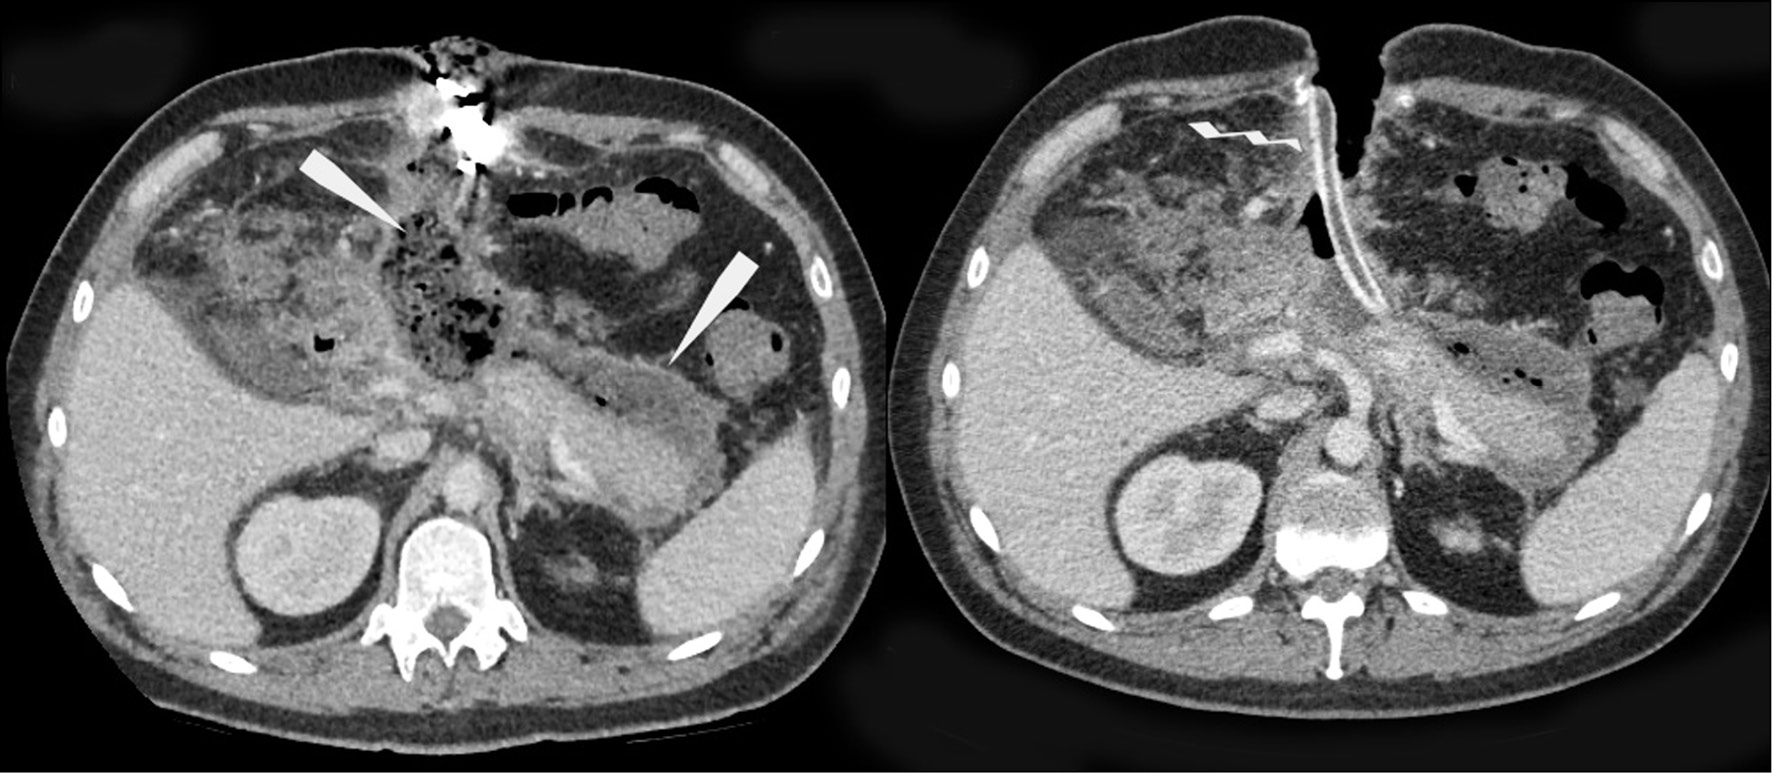

The control TO and AO CT (February 14; February 21, 2018) revealed a decrease in the left-sided hydrothorax and resolution of the area of consolidation in the lower lobe of the left lung, as well as a decrease in effusion in the peripancreatic tissue and infiltrative changes in the fatty tissue of the abdominal cavity (Fig. 4).

Fig. 4. Computed tomography of the abdominal cavity organs with intravenous contrast: enveloped infiltration and fluid accumulation in the peripancreatic adipose tissue, decreased in dynamics (image on the left, arrows), hemostatic sponge in the cavity of the enveloped contents; drainage tube (image on the right, zigzag arrow). Further formation of a thin contrasting capsule along the course of the infiltration zone is noted in the dynamics.